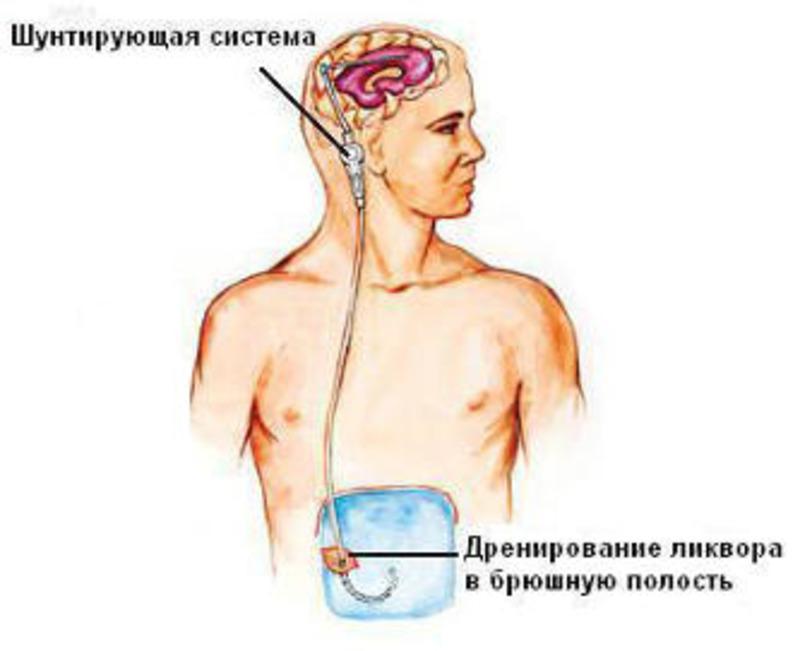

Вентрикуло-перитонеальный шунт: Показания и применение

Раздел: Фотоальбом решений